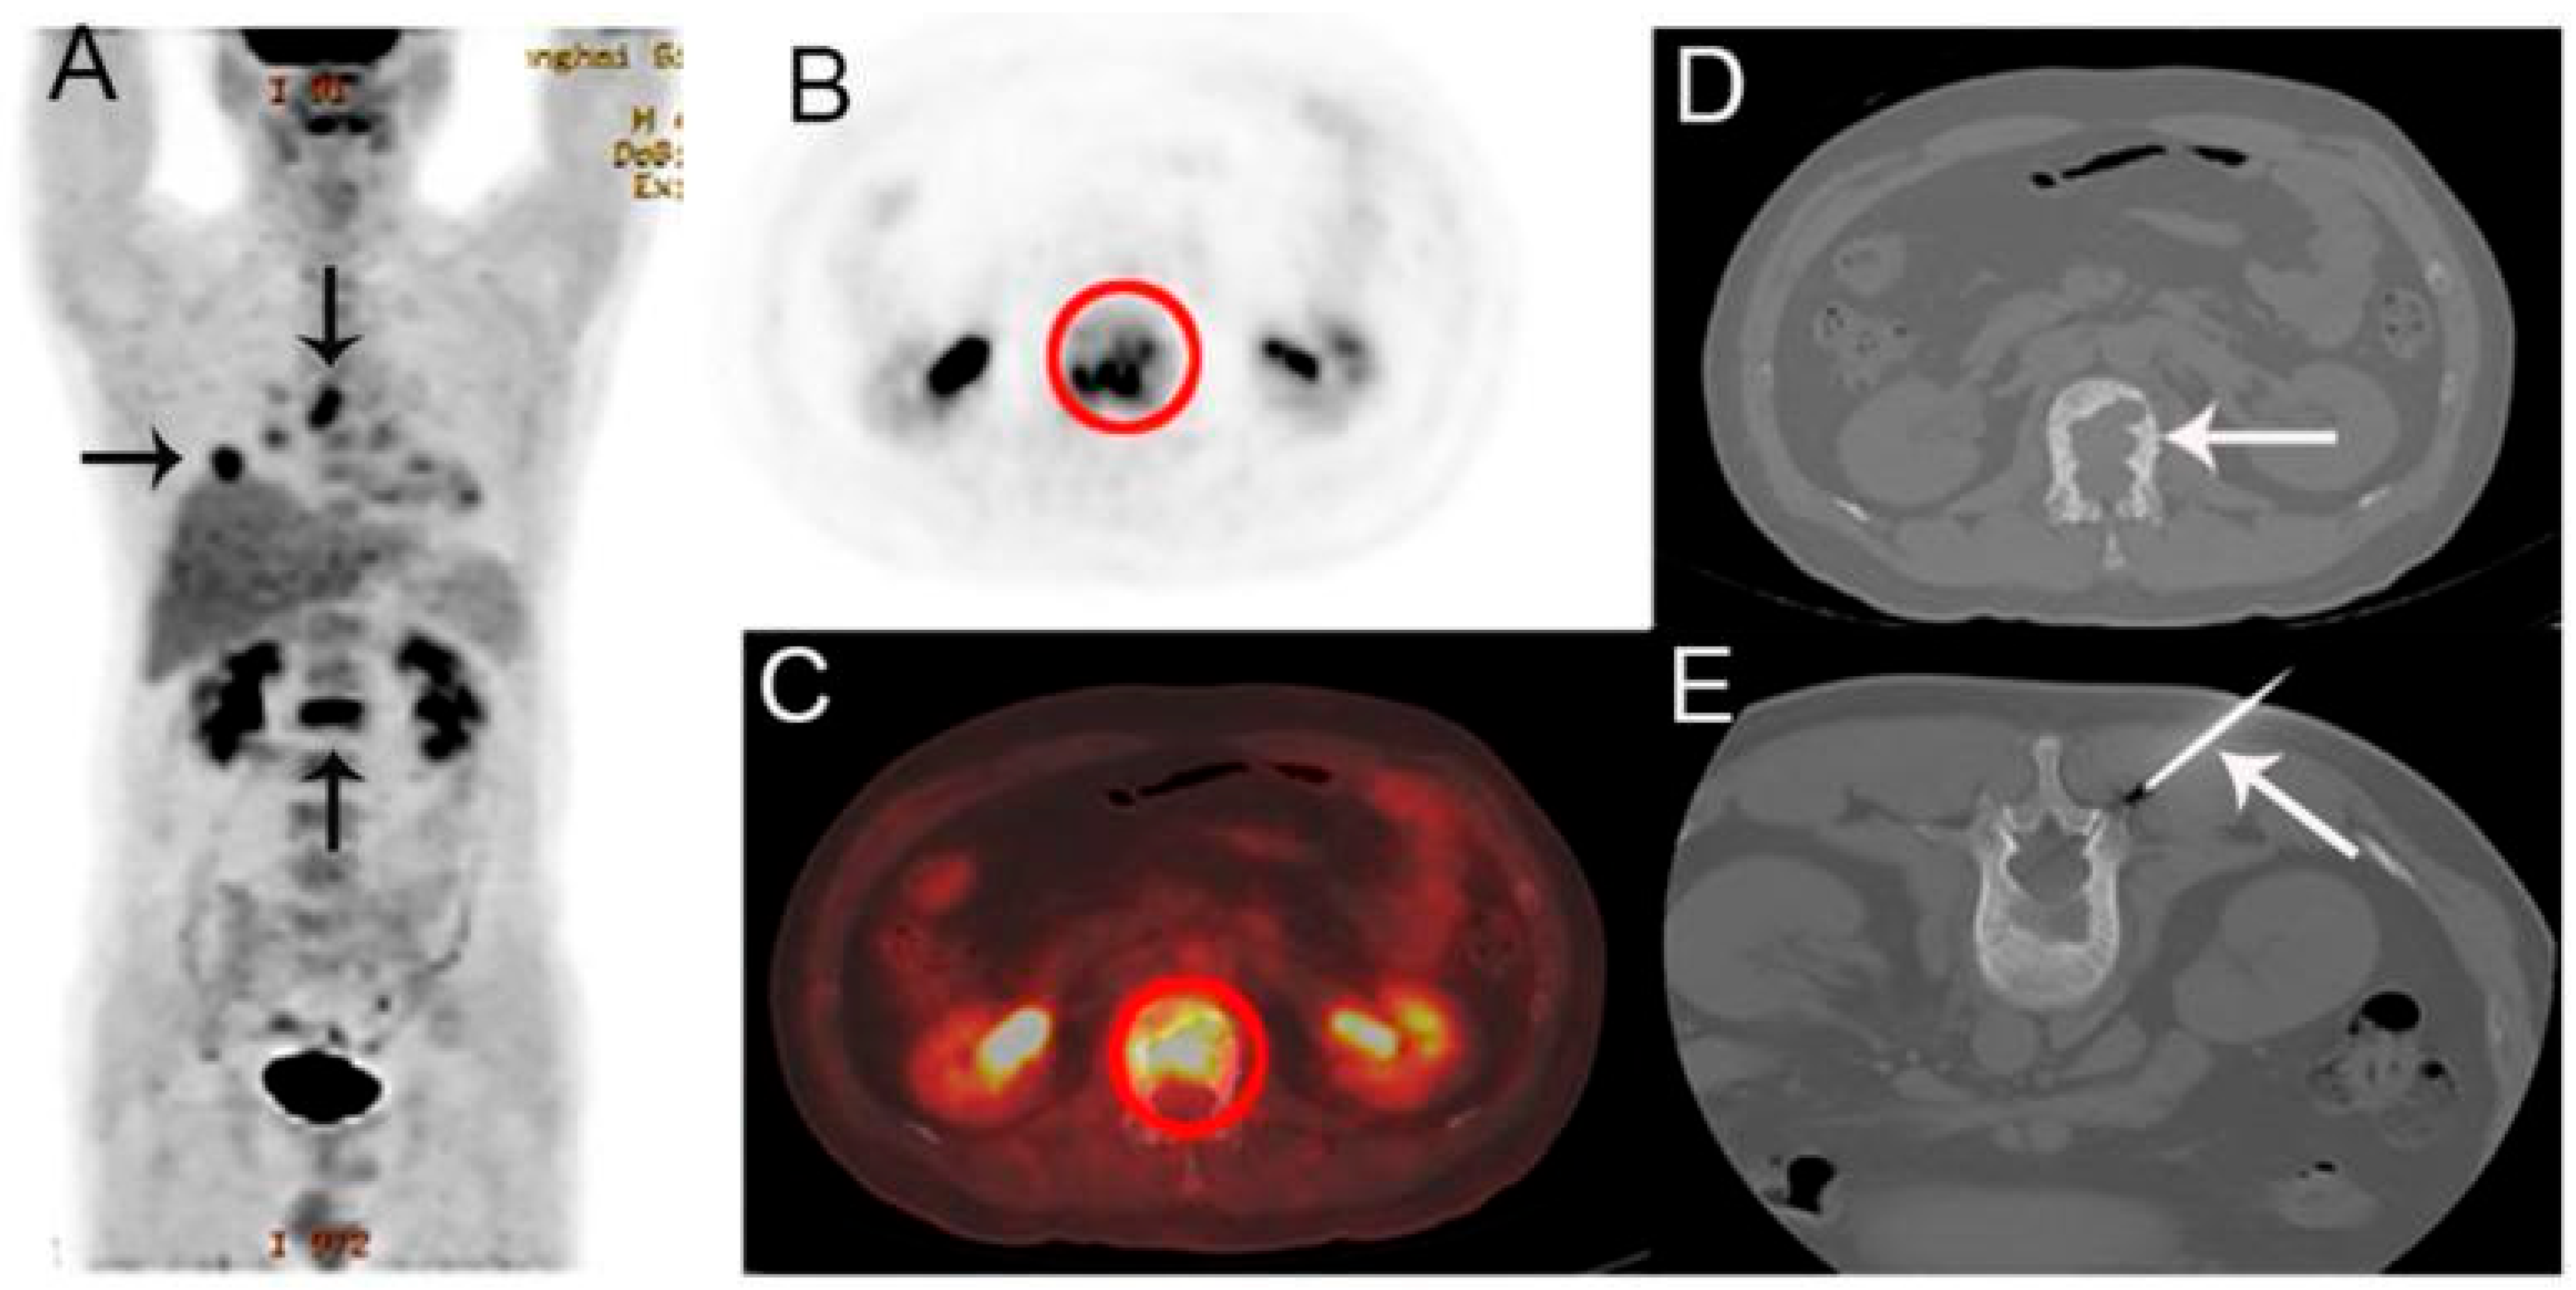

4.8. Tumor-Induced Osteomalacia (TIO)